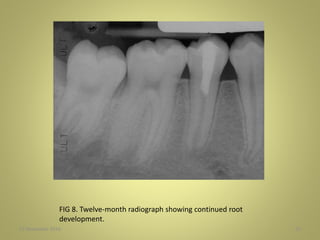

FIG 8. Twelve-month radiograph showing continued root

development.

27 November 201655 FIG 8. Twelve-month radiograph showing continued root development.